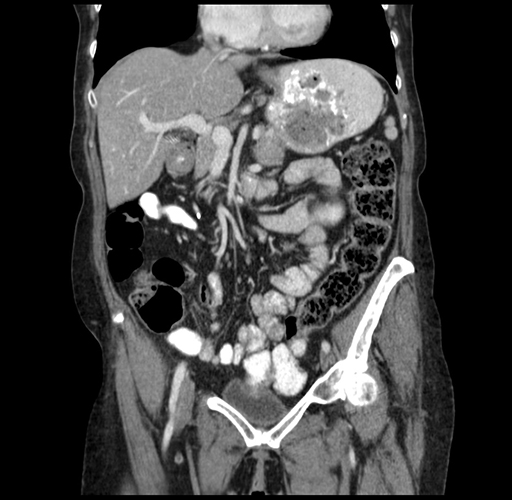

Coronal Venous